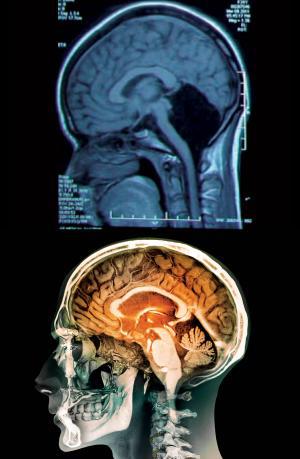

Cerebelul, numit şi „creierul mic”, are un ţesut mai compact faţă de restul creierului, reprezintă doar 10% din volumul total al creierului, dar conţine 50% din neuroni.

Funcţia principală a cerebelului este de a controla echilibrul şi mişcările voluntare, dar are un rol şi în învăţarea limbajului şi a mersului.